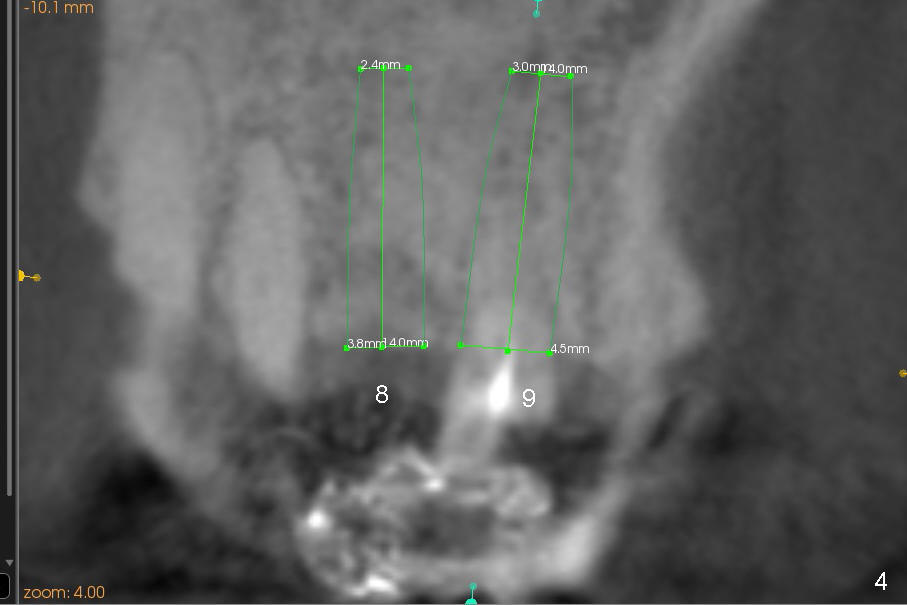

Buccal atrophy at the site of #8 dictates a smaller implant than that of #9 (Fig.4-7).